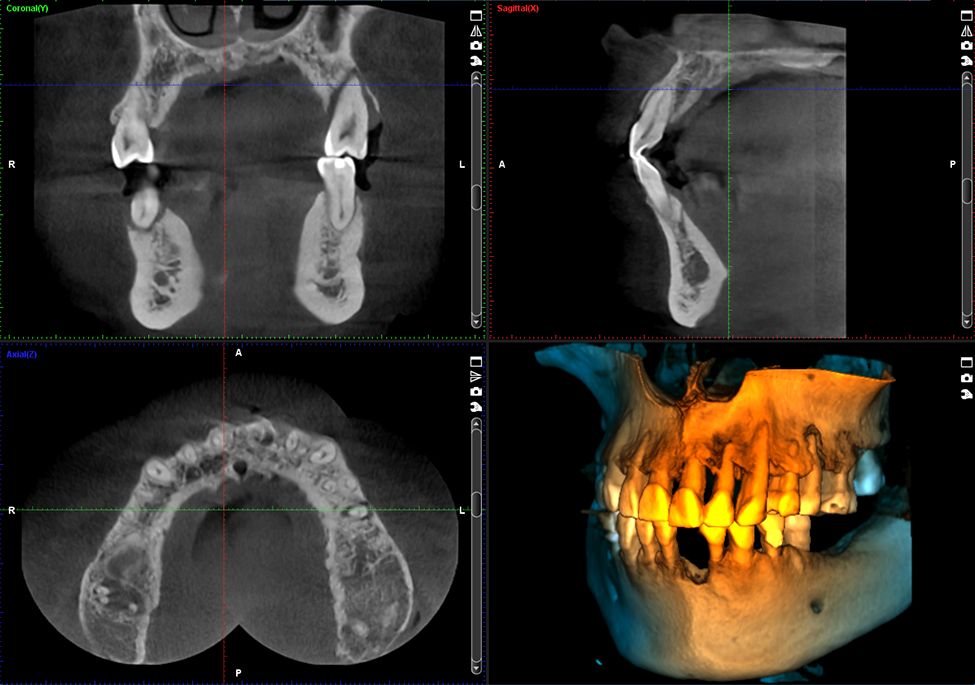

Obrazy Kliniczne Planmeca ProMax 3D s

Szczegółowe obrazowanie 3D

Specjalny tryb obrazowania endodontycznego pozwala na tworzenie szczegółowych, trójwymiarowych zdjęć. Woksele o rozdzielczości 75 μm zapewniają wyjątkową jakość obrazu, uwzględniając nawet najdrobniejsze detale.

Planmeca ProMax® 3D umożliwia uzyskanie kompletnych, niezwykle szczegółowych danych obrazowych, zapewniając precyzyjne odwzorowanie anatomii pacjenta. To rozwiązanie stanowi doskonały wybór dla placówek, które rozpoczynają pracę z technologią CBCT.

• Obrazuje małe obszary z dużą szczegółowością, idealny do implantów i leczenia kanałowego.